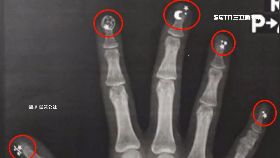

手照X光驚見星月 網:美少女戰士?

一名網友PO文說他的老婆手受傷去照X光,結果卻驚呆了...